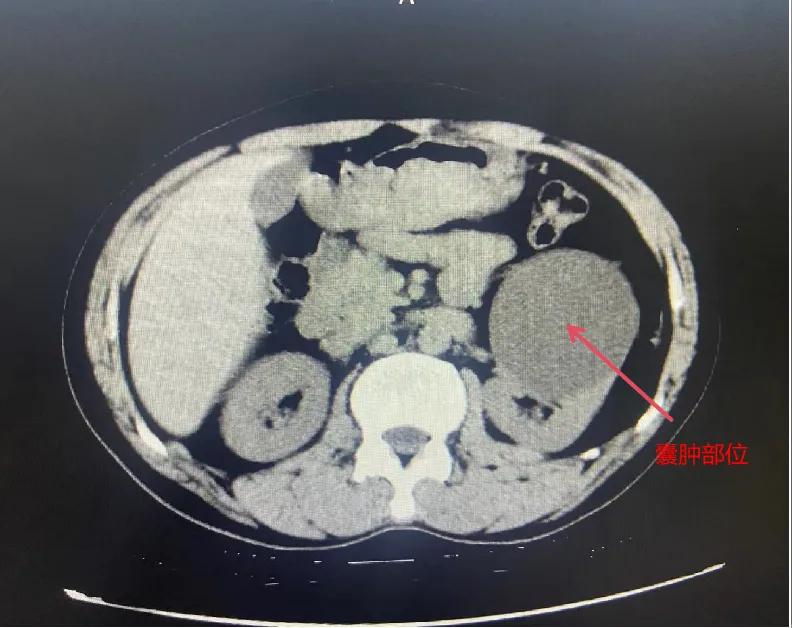

漯河市骨科醫(yī)院泌尿外科開展后腹腔鏡下腎囊腫去頂減壓術(shù)

近日,漯河市骨科醫(yī)院(漯河醫(yī)專二附院、漯河市立醫(yī)院)連續(xù)收治2例腎囊腫患者。泌尿外科主任閆衛(wèi)甫和副主任醫(yī)師王金柱等醫(yī)師團(tuán)隊經(jīng)討論研究后,決定為患者采取后腹腔鏡下腎囊腫去頂減壓術(shù),經(jīng)過手術(shù)室、麻醉科等科室大力配合成功完成手術(shù)。

腎囊腫是一種常見的腎臟良性疾病,其發(fā)病率逐年增加。近年來隨著腹腔鏡技術(shù)的迅速發(fā)展,后腹腔鏡下腎囊腫去頂減壓術(shù)成為治療腎囊腫的主要方法。該手術(shù)具有創(chuàng)傷小,手術(shù)時間短,術(shù)中出血少,術(shù)后康復(fù)快,出院時間短等優(yōu)點,并且術(shù)后復(fù)發(fā)率低,被認(rèn)為是治療腎囊腫的理想術(shù)式。(盧 闖 聶方方 劉 旭 袁錦鈺)